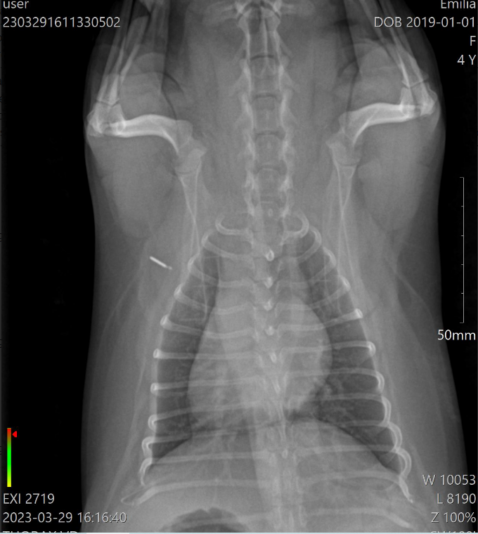

Chronic Cough problem with underline heart disease?

i upload this post in order to discuss one of my cases with you

Its about a yorkshire terrier, 3 years old, female, sterilised, that has coughing problems for 6 months. According with the owner, the problem didnt start 6 months ago, but earlier. But the last 6 months is really getting worse. Before it was once per week…